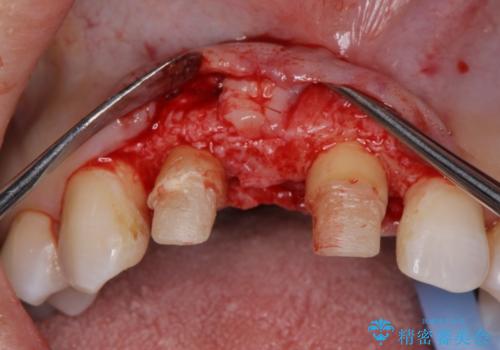

現在装着されているブリッジを除去したところ、歯ぐきよりも上に存在する歯質(縁上歯質)が少なく、土台の形態の悪さや不適合などさまざまな問題があります。

根管治療を行ったのち、歯周外科を行うことで、欠損部の歯ぐきの厚みを出し、縁上歯質を獲得することで、長期的な予後の見込めるブリッジを製作できる環境を整備していきます。